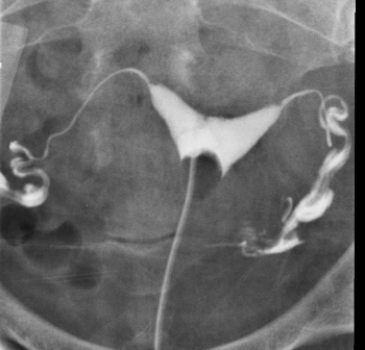

Male and Female Urinary Tract and Male Genital Tract